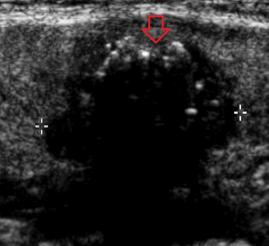

- Tiroid iltihabı (Hashimoto)

- Hashimato'da lazer tedavisi: İlaç dozlarının azaltılması veya kesilmesi ve kilo kontrolü !!!

- Hashimoto hastalığında destek tedavileri